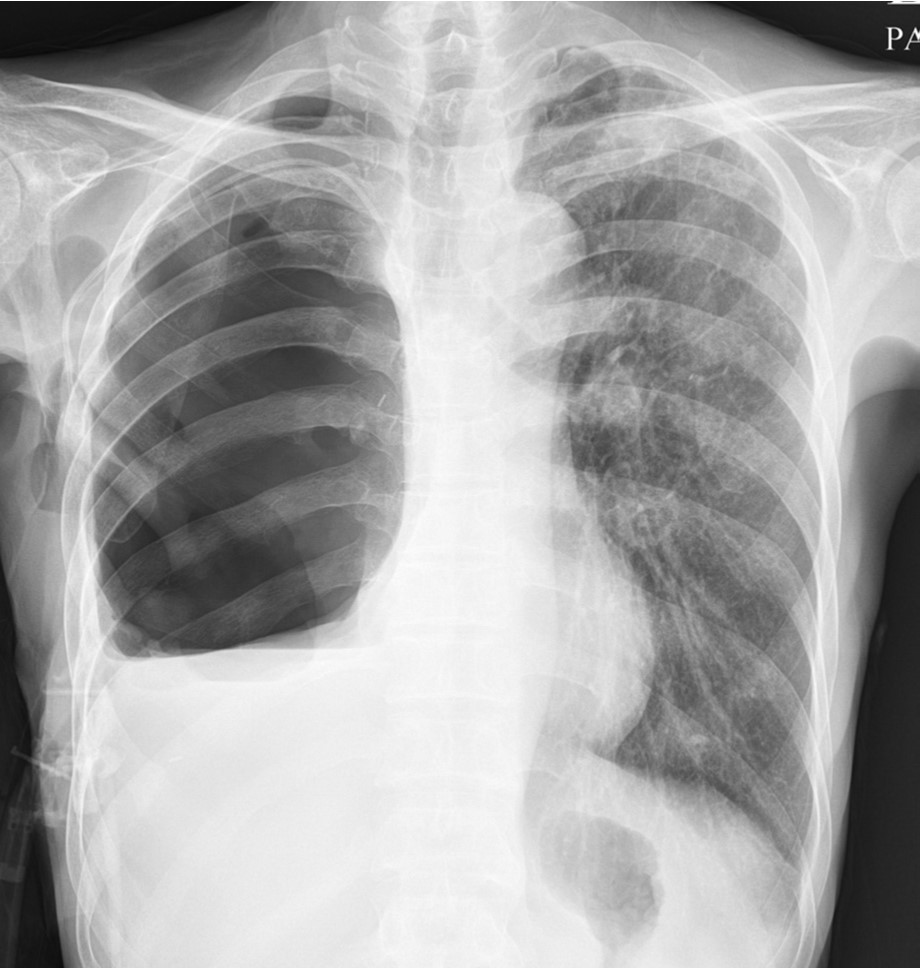

Fig. 3.

Chest radiograph obtained after pneumonectomy revealed chest tube and fluid retention in the right thoracic cavity.